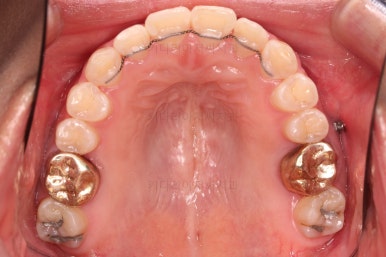

부산안면비대칭 첫 단꼐로 악궁확장 장치를 했어요.

비대칭이 있어서 한 것도 아니고, 공간이 부족해서 한 것도 아니에요.

비발치로 하고자 해서 한 것도 아니에요.

단순히 위아래의 조화가 안맞을 때 하는 것이 악궁확장이며 이번 환자분도 위아래의 조화가 안맞아서 악궁확장장치를 사용했고, 그 근거는 CT 분석을 통해서 이루어져요.

악궁확장 이후에 교정장치를 부착하고 치열을 가지런하게 해줘요.

이번에 사용한 장치는 엠파워 메탈이라고 하는 자가결찰 메탈 장치입니다.